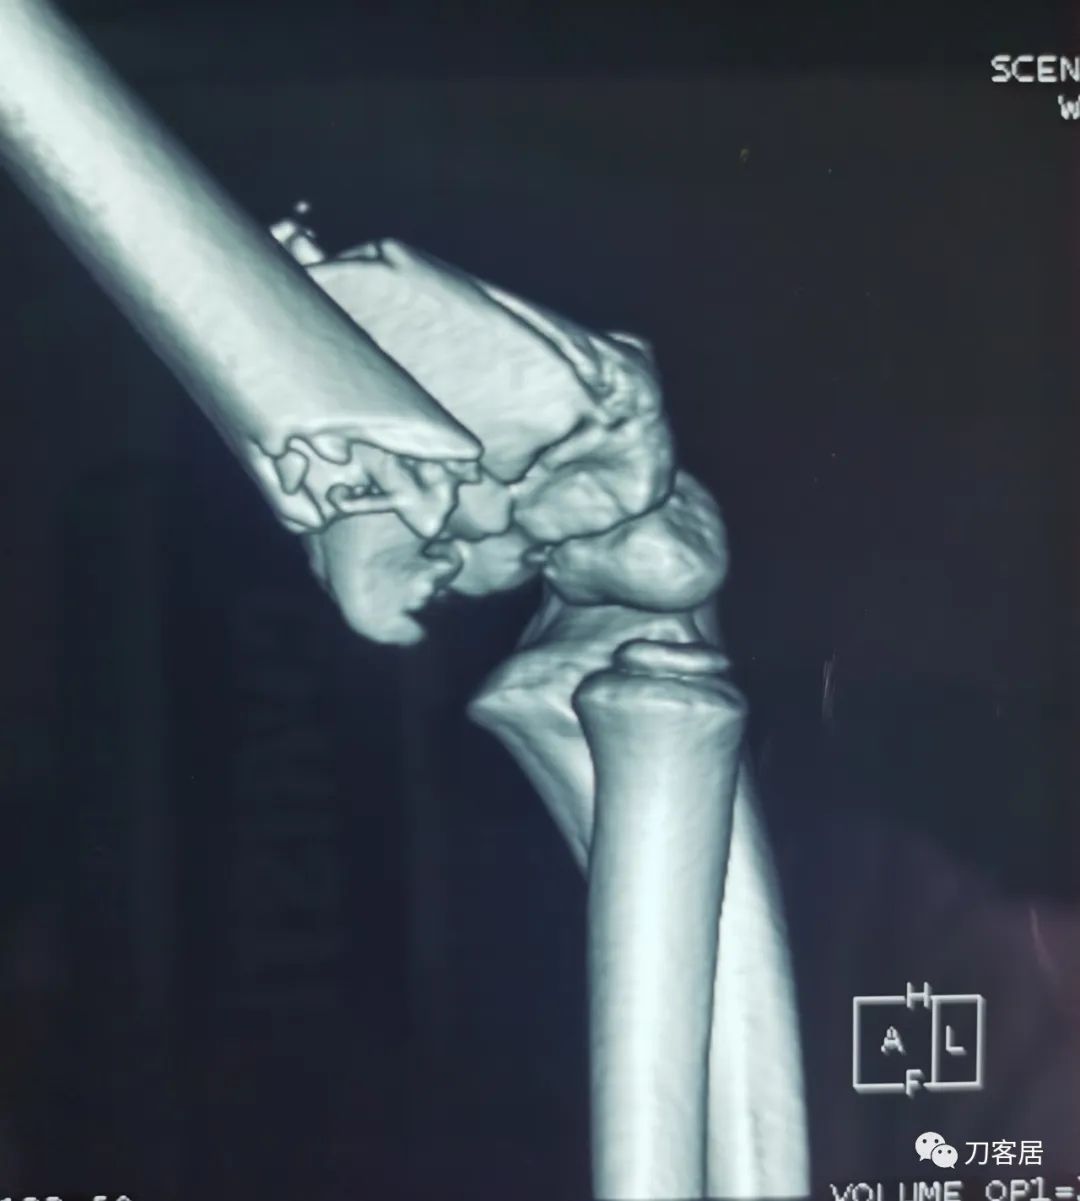

查体:左侧肘关节肿胀明显、疼痛、畸形,局部可见明显青紫瘀斑,左肘关节活动受限,肱骨远端环形压痛(+),局部可及异常活动及骨擦感形成,左上肢末梢桡动脉可触及,左侧腕关节及拇指背伸活动受限,左侧虎口区感觉麻木。辅助检查:自带X线及CT片示:左肱骨髁间粉碎性骨折。

入院诊断:1. 左肱骨髁间粉碎性骨折;2.左肱骨远端骨骺损伤;3. 左桡神经损伤。

20210922当地省中医院三维CT04